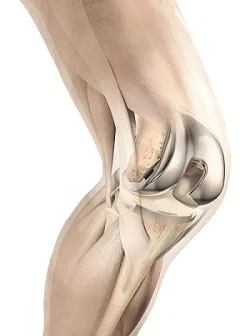

Коліно є однією з найбільш задіяних частин опорно-рухової системи людини. І водночас це досить...